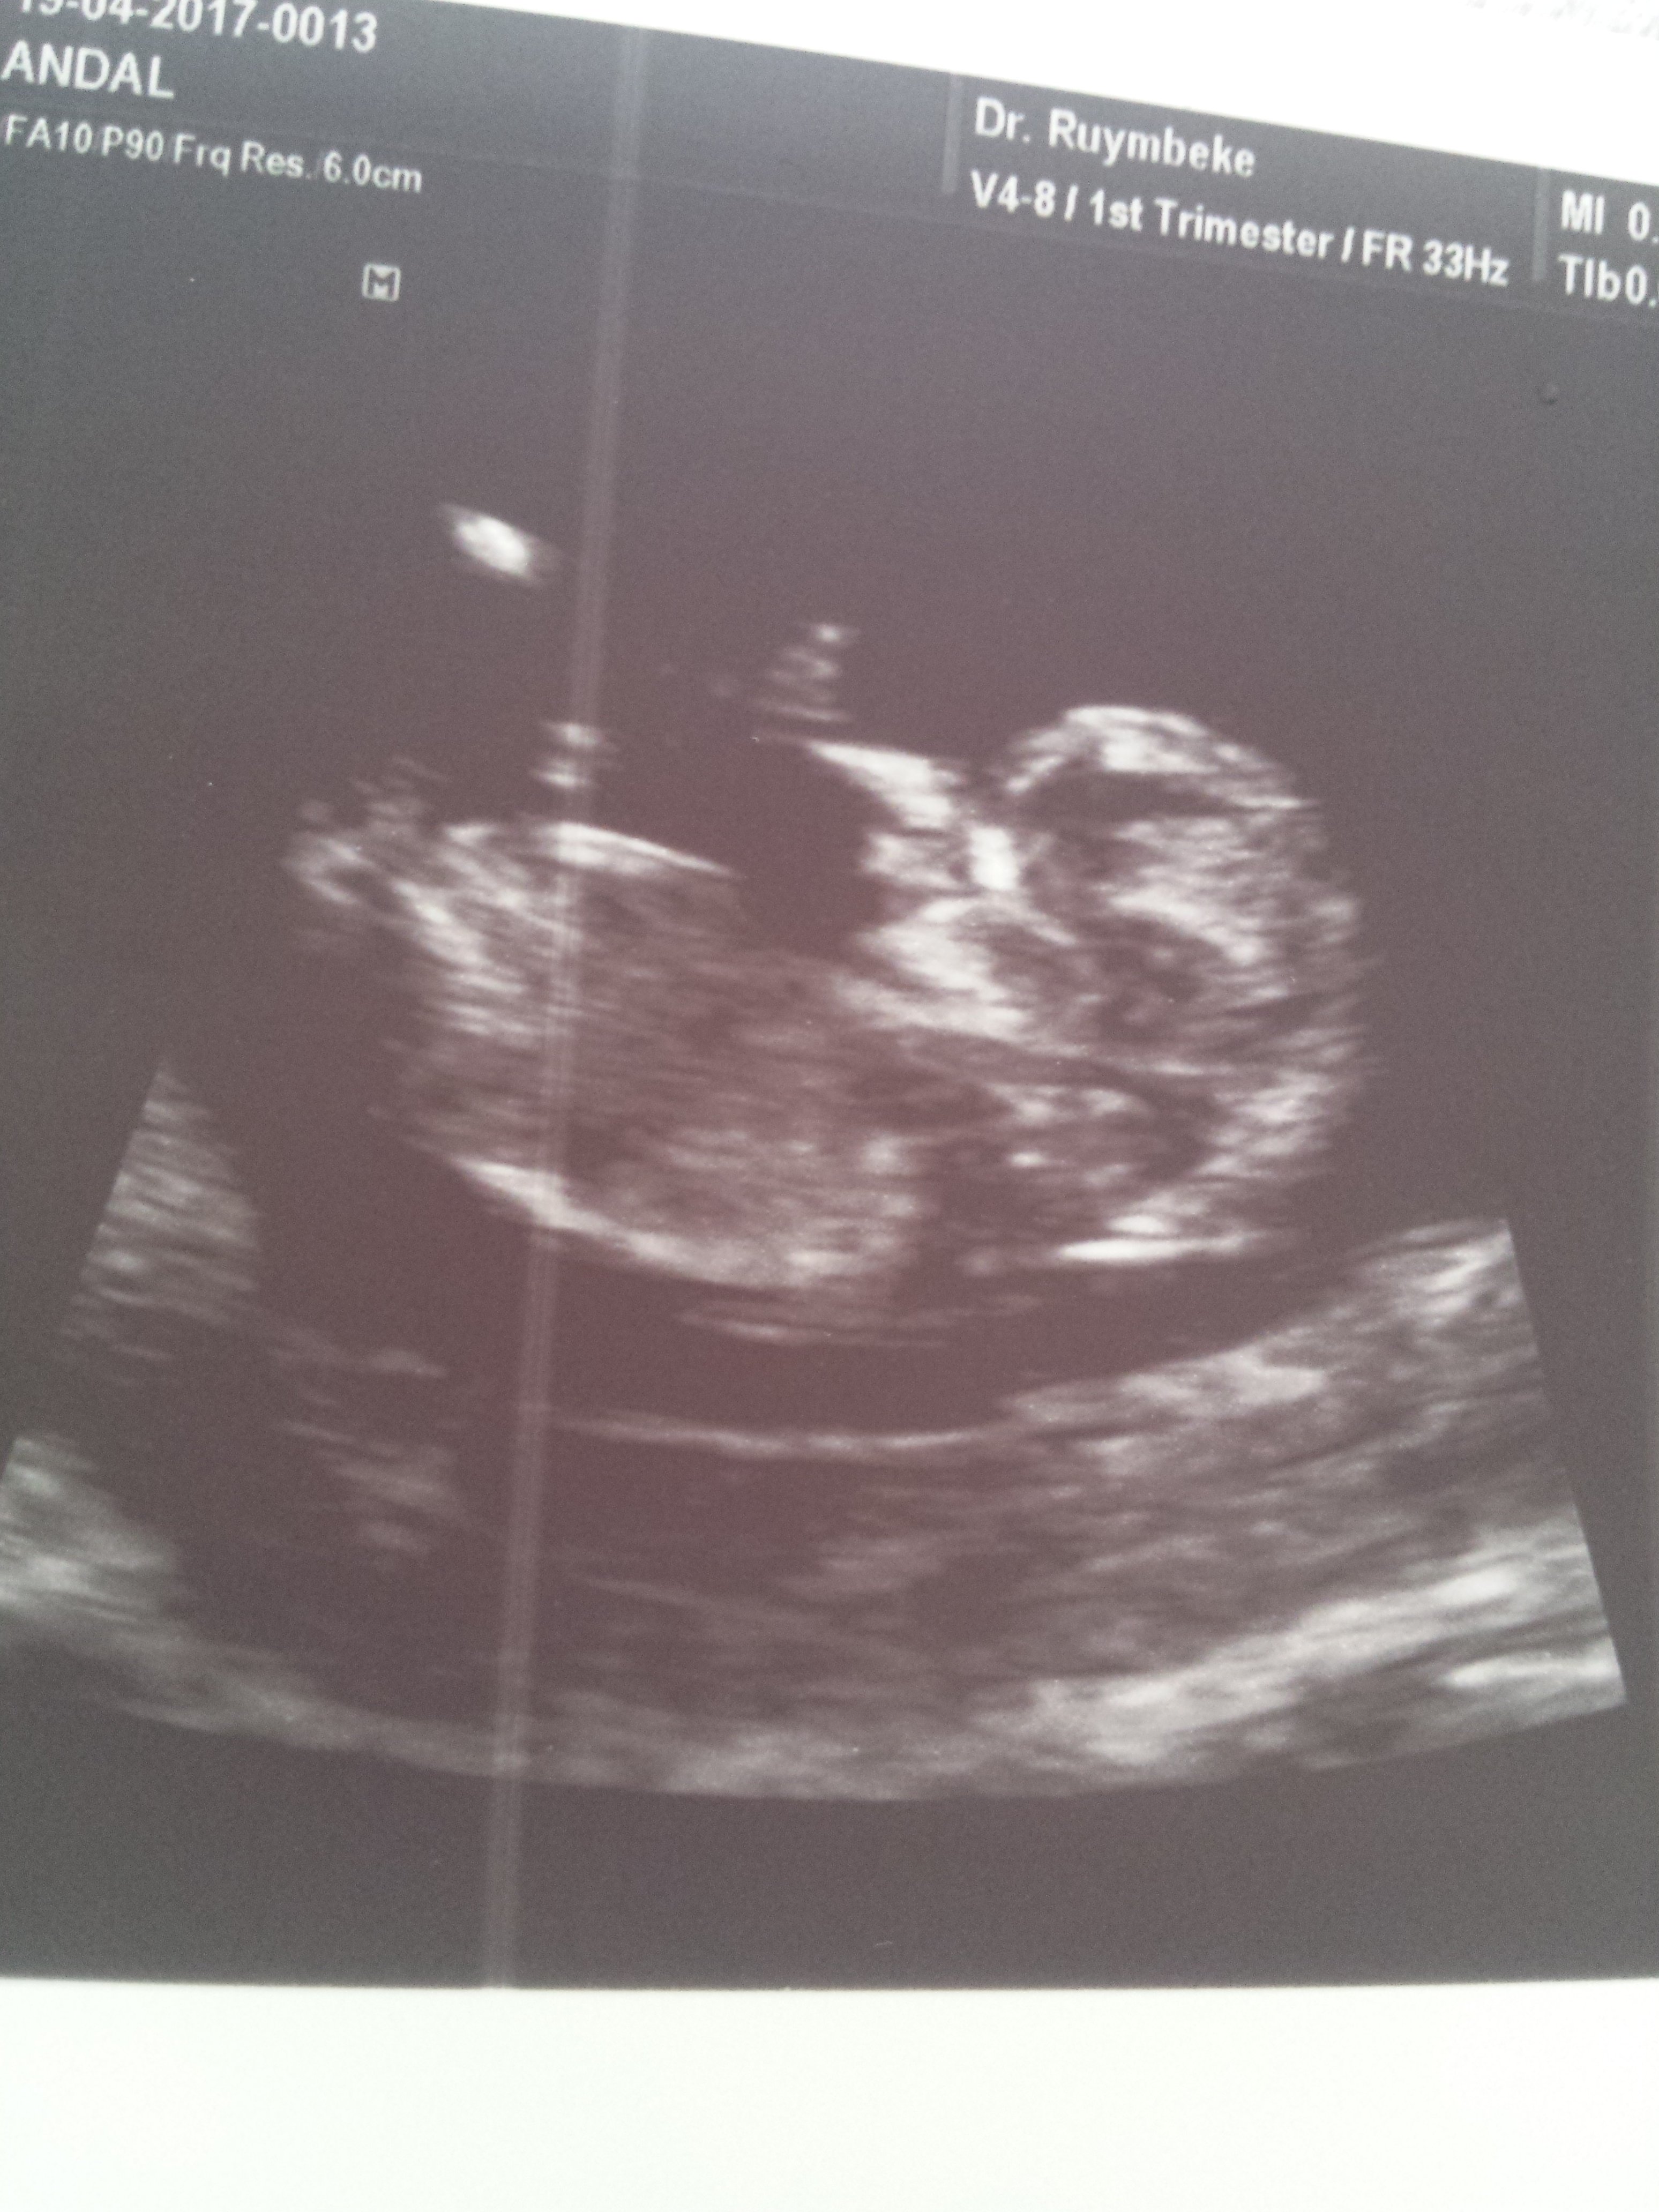

1 1234tmm Yeni Üye Üye 29 Nisan 2017 #264 Ekli dosyayı görüntüle 76263 Ekli dosyayı görüntüle 76264 Ekli dosyayı görüntüle 76264

1 1234tmm Yeni Üye Üye 29 Nisan 2017 #266 Ekli dosyayı görüntüle 76265 11+4 dusuncelerinixi alabilirmiyim *BEYZA*' Alıntı: Yorum yaptığınız yerde fotoğraf yükle butonu var.Yüklemeyi ordan yapıcaksınız. Genişletmek için tıkla ... Cok tesekkur canim sanirim oldu.

Uzman SühaN Administrator 29 Nisan 2017 #267 Merhaba, Nub çıkıntısı pek net değil fakat bebeğinizin cinsiyetinin kız olduğunu düşünüyorum.Sağlıklı gebelik geçirmeniz dileği ile.

Merhaba, Nub çıkıntısı pek net değil fakat bebeğinizin cinsiyetinin kız olduğunu düşünüyorum.Sağlıklı gebelik geçirmeniz dileği ile.